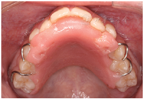

患者就诊时上颌配戴斜面导板

患者就诊时上颌配戴斜面导板(2)曲面体层X线片:恒牙列,18—28,38—48;双侧髁突形态基本对称,骨皮质连续;牙槽骨未见明显异常(图1)。头颅侧位X线片:患者处于颈椎骨龄一期,有80%以上的生长潜力[1, 2](图1)。头影测量示,上牙槽座角87.7°,下牙槽座角80.8°,ANB角(上牙槽座点、鼻根点与下牙槽座点构成的角)6.9°,下颌骨体长与前颅底长之比为104.7%,Wits值(上、下牙槽座点在功能